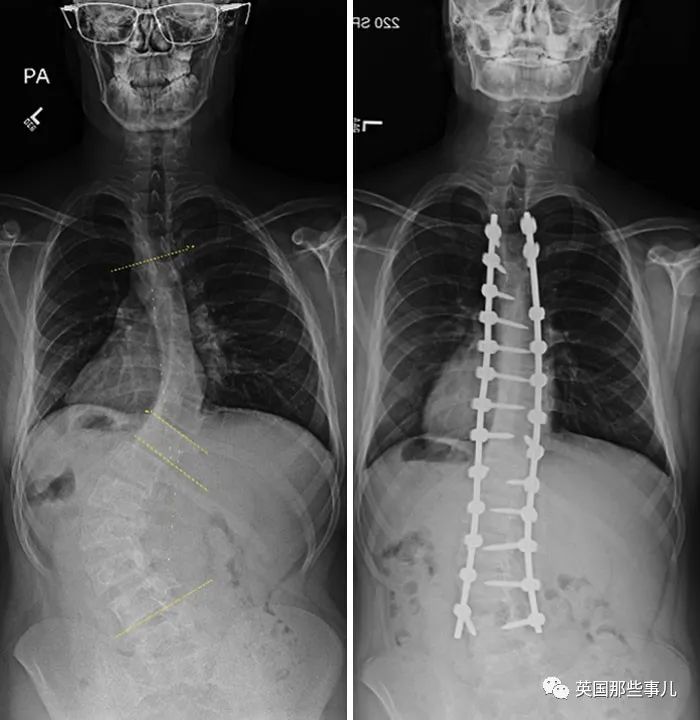

患有脊柱側(ce) 彎的人,手術前後的對比